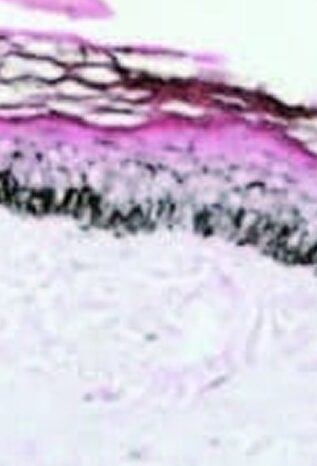

- Induziert den Keratinozytenumsatz und stellt die normale Pigmentaktivität der Melanozyten in überpigmentierten Bereichen wieder her.

- Dies geschieht an der dermoepidermalen Junktionszone (DEJ).

- Der Bereich zwischen der dermoepidermalen Junktionszone und der flachen Dermis ist die Zieltiefe für die Mikronadelung.

- Die Aktivierung, Migration und/oder Proliferation von Melanozyten in hypopigmentierte Bereiche an der dermoepidermalen Junktionszone (DEJ) soll induziert werden. Diese oberflächliche Dermis stellt die Zieltiefe dar.

- Darüber hinaus stimuliert ein mechanisches Trauma die Migration der Melanozyten von den pigmentierten Bereichen zu den unpigmentierten Bereichen.

- Durch Mikroneedling kann die Anzahl der Pigmentzellen erhöht und die Pigmentproduktion angeregt werden.

- Studien in der Fachliteratur deuten darauf hin, dass sechs oder mehr Behandlungen erforderlich sein können, um eine Besserung festzustellen.